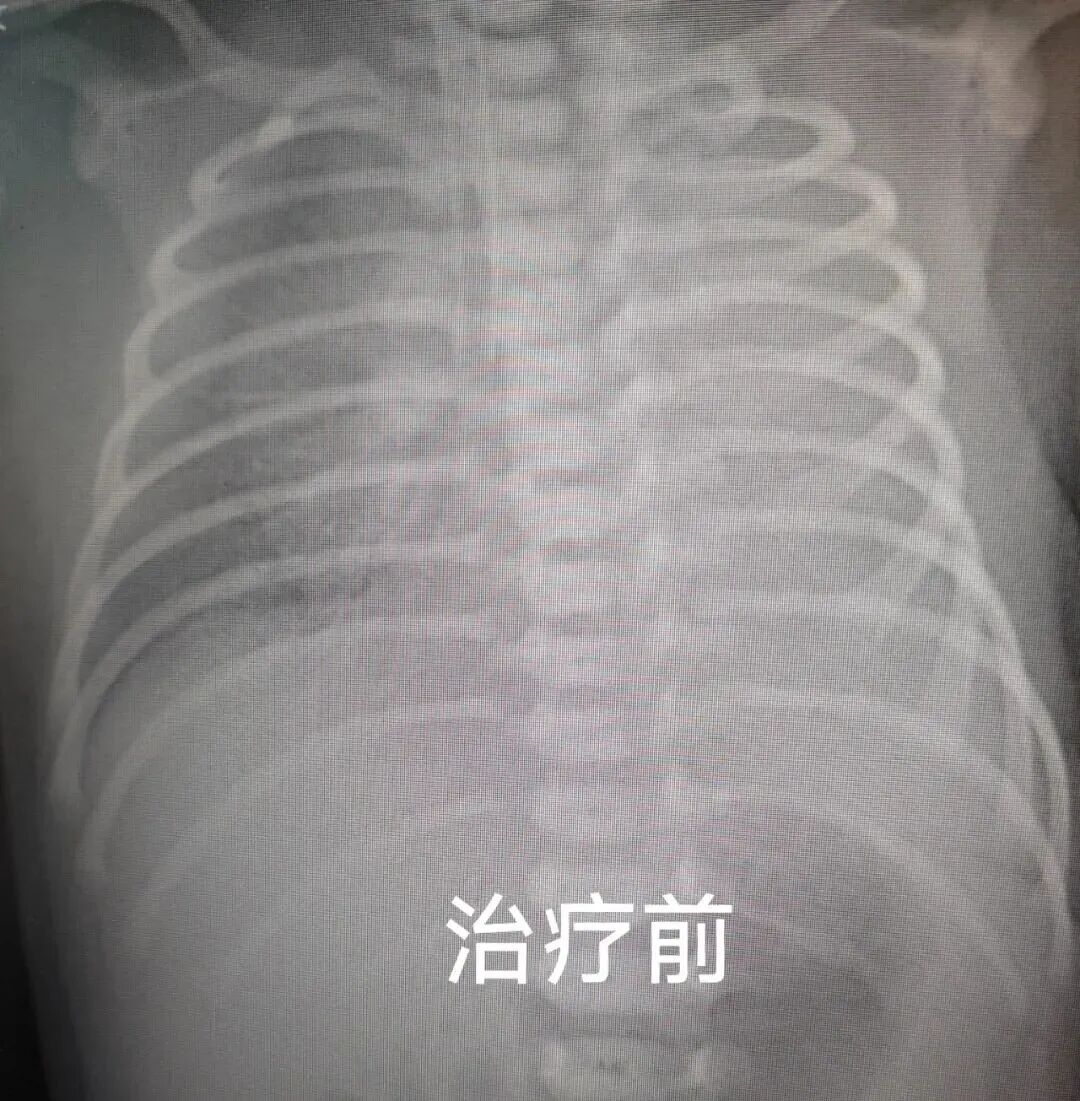

入科检查结果让医护团队倍感压力:床旁胸片显示患儿左侧肺部弥漫性透亮度降低,确诊为“重度肺不张”;同时,气管插管内持续引流出鲜红色血液,明确诊断新生儿肺出血。